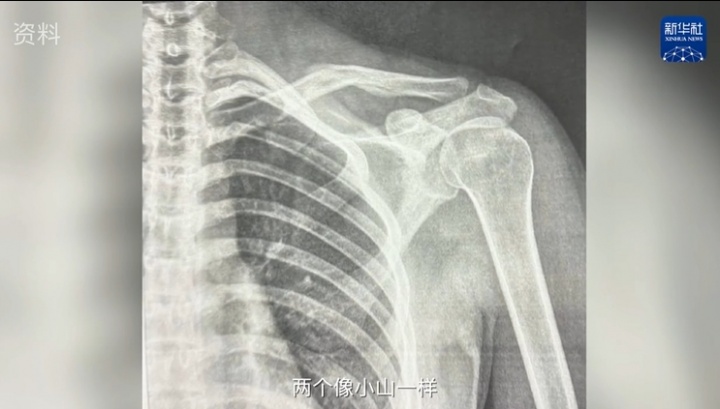

完了以后不是有亚冬会嘛,我就是又太早上雪了。我那次摔的时候就锁骨断了。其实这个是锁骨第二次断,你如果有直接的光对着它,你能看见两个像小山一样长在骨头上。还好不需要做手术。所以我就是养它养了大概3个月。”